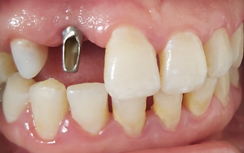

On the day of implant placement : (Figures 6,7). The implant was placed 7 years after the fall of 12 (loss of tooth due to trauma) in a completely healed site. 10 days after implant placement: (Figure 8). A temporary mesially extended bridge supported on 13 was cemented .

Figure 6 Placement of the implant + screw cover + suture.

6 months after implant placement: (Figure 9). A second surgical step for the placement of the healing screw to shape the soft tissue, especially the emergence profile.

Figure 9 Placement of the healing screw (6 months after osseointegration).